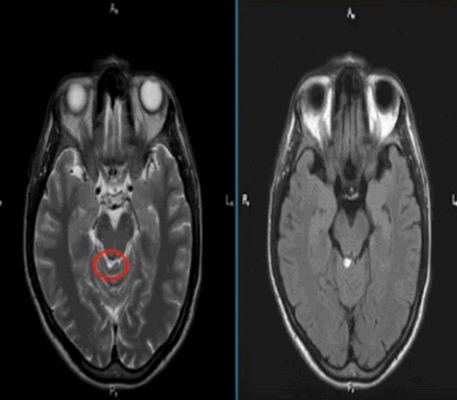

Липома четверохолмной цистерны на МРТ (обведена кругом)